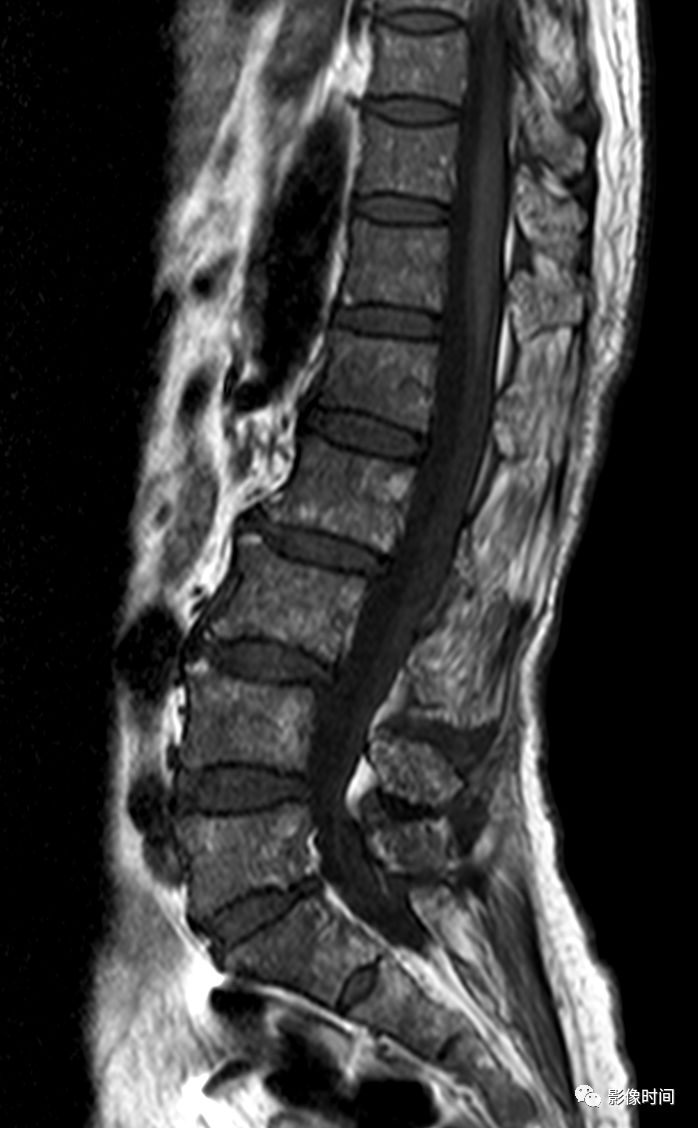

MR 液体征

MR 液体征为椎体压缩骨折 MRI 征象,表现为液体敏感序列中在塌陷椎体水肿背景上出现局灶性、线样或三角形更高信号(黄箭),信号强度与脑脊液相仿,T2WI 亦可显示(黄箭)。常提示良性压缩性骨折。

典型病例

67 岁男性,骨质疏松压缩性骨折。MRI 的 T2WI 及脂肪抑制像示两个压缩椎体内可见高信号,与脑脊液相仿(红箭示)。